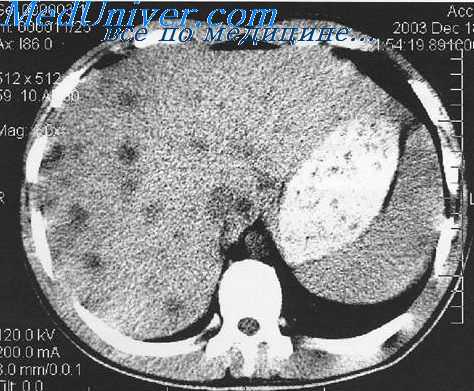

- МСКТ органов брюшной полости. При помощи послойного исследования тонкими срезами (0,625 мм) с последующим трехфазным контрастным усилением визуализируют взаимное расположение и размеры печени, поджелудочной железы, желчного пузыря. Компьютерная томография дает возможность выявить камни и новообразования, вызывающие развитие желтухи.